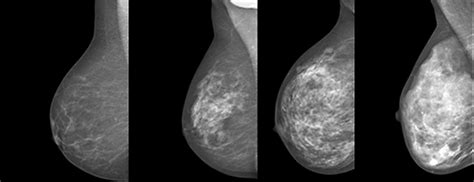

Histologisk grad: Tubulär formation ( poäng), kärnatypi ( poäng), mitoser ( poäng) Grad 1= poäng, grad 2= poäng, grad 3= poäng. Oncotype DX assesses 16 cancer-related genes and 5 normal comparator reference genes, and is therefore sometimes known as the gene assay. These multigene assays, some partially and some completely commercialized, have been scientifically reviewed to compare them with other standard breast cancer classification methods such as grade and receptor status. Istället för att basera indelningen på genuttryck används idag i första hand proteinuttrycket mätt med immunohistokemi IHC för en mer pragmatisk indelning. Invasiv duktal cancer grad 1

Graderingen av preoperativa biopsier är preliminär och kan komma att ändras vid bedömning på operationspreparatet. Mikroinvasiv bröstcancer graderas ej. En specifik grad (NHG1, 2 eller 3) bör anges och inte ett intervall (t ex NHG ). I svårbedömda fall, vid mycket små tumörer och vid biopsier kan prefixet ”närmast” anges. Äggstockscancer inklusive äggledarcancer och primär peritoneal karcinomatos icke-mucinös, icke-borderline oavsett ålder. Treatment for hypertensive retinopathy. Trippelnegativ bröstcancer grad 3 överlevnad

Det innebär att graderna för in situ motsvarar inte graderna för invasiv cancer, men inom duktal cancer in situ är det så att grad 3 är mer avvikande än grad 1. MammaPrint and BluePrint [ edit ]. Mjölkgångspapillom — blodtillblandat eller mörkfärgat sekret från en mjölkgång. Stage Information for Breast Cancer.